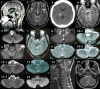

Methods: Fifteen patients with upbeat nystagmus received full neuro-ophthalmological evaluation by the senior author. Nystagmus was observed using video Frenzel goggles and recorded with video-oculography. Brain lesions were documented with MRI.

Results: LESIONS RESPONSIBLE FOR NYSTAGMUS WERE FOUND THROUGHOUT THE BRAINSTEM, MAINLY IN THE PARAMEDIAN AREA: in the medulla (n=8), pons (n=3), pons and midbrain with or without cerebellar lesions (n=3), and midbrain and thalamus (n=1). Underlying diseases comprised cerebral infarction (n=10), multiple sclerosis (n=2), cerebral hemorrhage (n=1), Wernicke encephalopathy (n=1), and hydrocephalus (n=1). Upbeat nystagmus was mostly transient and showed occasional evolution during the acute phase. In one patient with a bilateral medial medullary infarction, the upbeat nystagmus changed into a hemiseesaw pattern with near complete resolution of the unilateral lesion. Gaze and positional changes usually affected both the intensity and direction of the nystagmus. A patient with a cervicomedullary lesion showed a reversal of upbeat into downbeat nystagmus by straight-head hanging and leftward head turning while in the supine position. Gaze-evoked nystagmus (n=7), ocular tilt reaction (n=7), and internuclear ophthalmoplegia (n=4) were also commonly associated with upbeat nystagmus.

Conclusions: In view of the responsible lesions and associated neuro-ophthalmological findings, upbeat nystagmus may be ascribed to damage to the pathways mediating the upward vestibulo-ocular reflex or the neural integrators involved in vertical gaze holding.